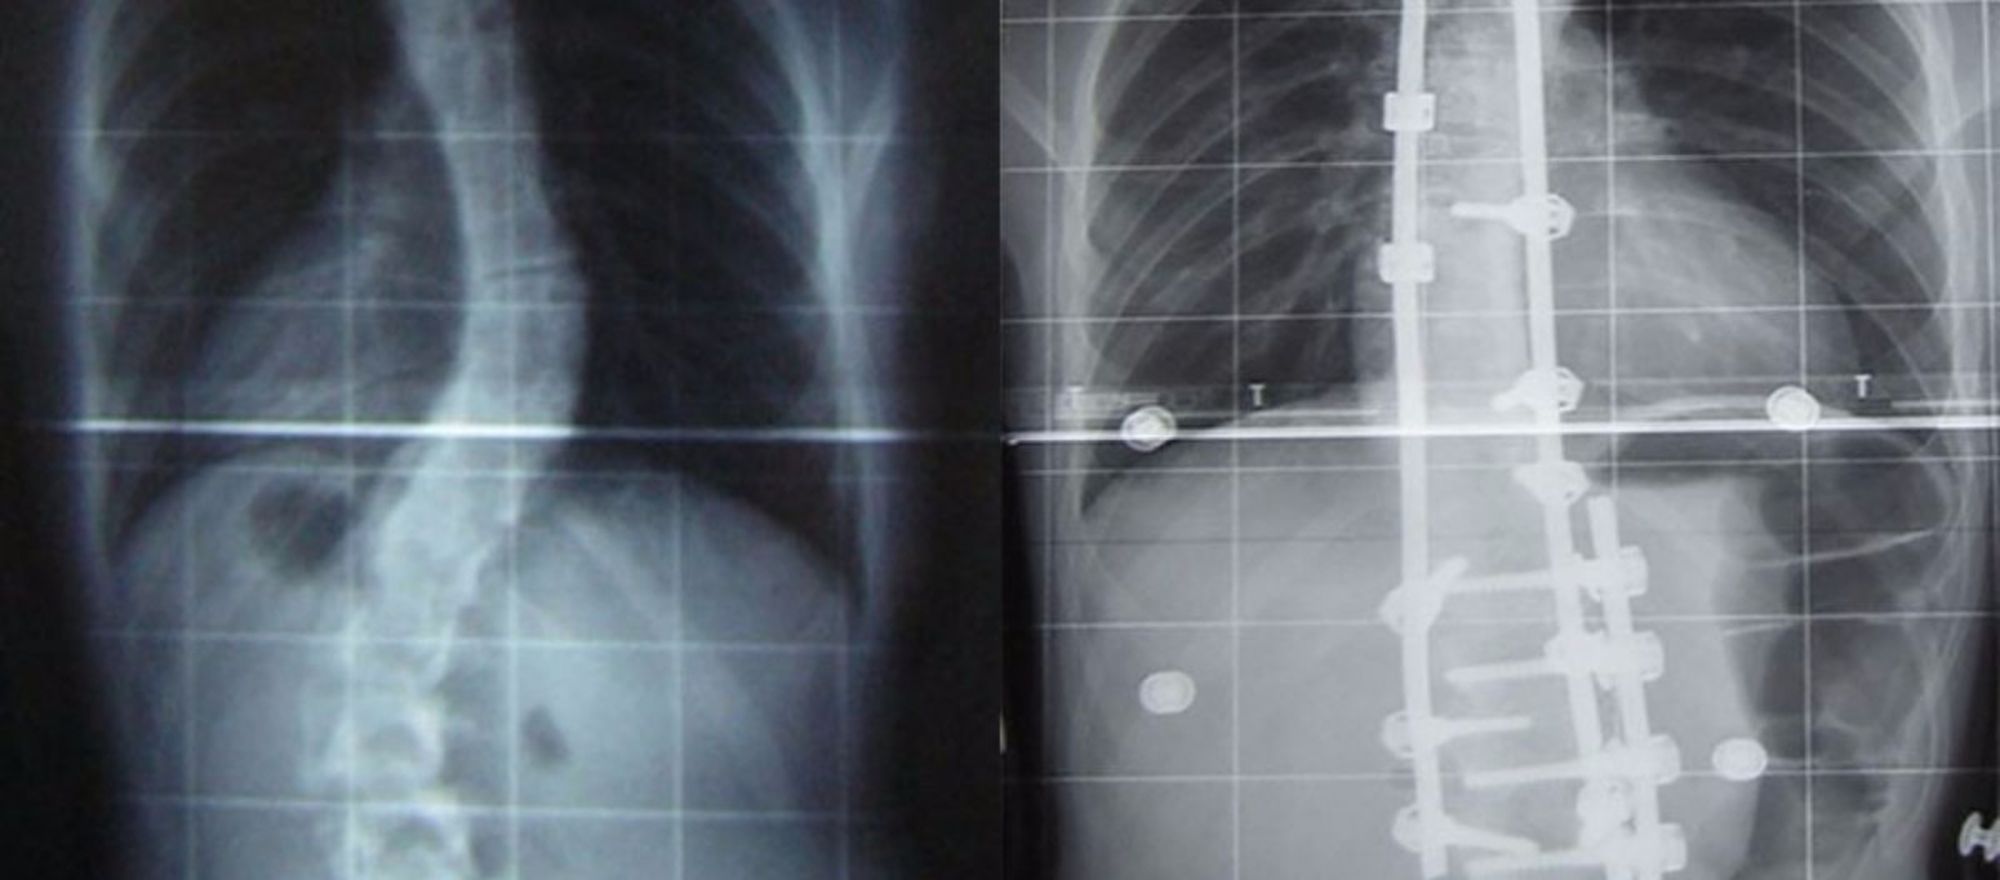

Skolyoz, yani omurga eğriliği, adından da anlaşılabileceği üzere gelişimsel olarak bir insanın omurgasının yamuk/eğri olması hastalığıdır. Aslında omurgamızın doğal bir kıvrımlı yapısı vardır; ancak "normal" şartların ötesine geçecek düzeyde, genellikle 3 boyutta da (en, derinlik ve uzunluk) meydana gelen kaymalar, omurganın şeklini bozar ve sorunlara neden olur. Fotoğrafta, sağ tarafta görülen budur.

Eğer ki fotoğraftaki gibi uç vakalar (eğriliğin 45-50 dereceyi aştığı vakalar) söz konusuysa, genellikle ameliyatla tedavi önerilmektedir. Bu da bizi sağ taraftaki fotoğrafa getirir. Sağdaki fotoğraf, soldaki gibi bir bireyin ameliyat sonrası omurgasının düzeltilmesi ve bu düzeltmeyi sürekli kılmak için yerleştirilen metal köprüleri göstermektedir. Ne yazık ki skolyozlu bir omurgayı genellikle tamamen düzeltmek mümkün olmamaktadır; ancak çoğu zaman yapılan düzeltmeler, eski hale göre fazlasıyla rahat yaşam standartları sağlamaktadır.